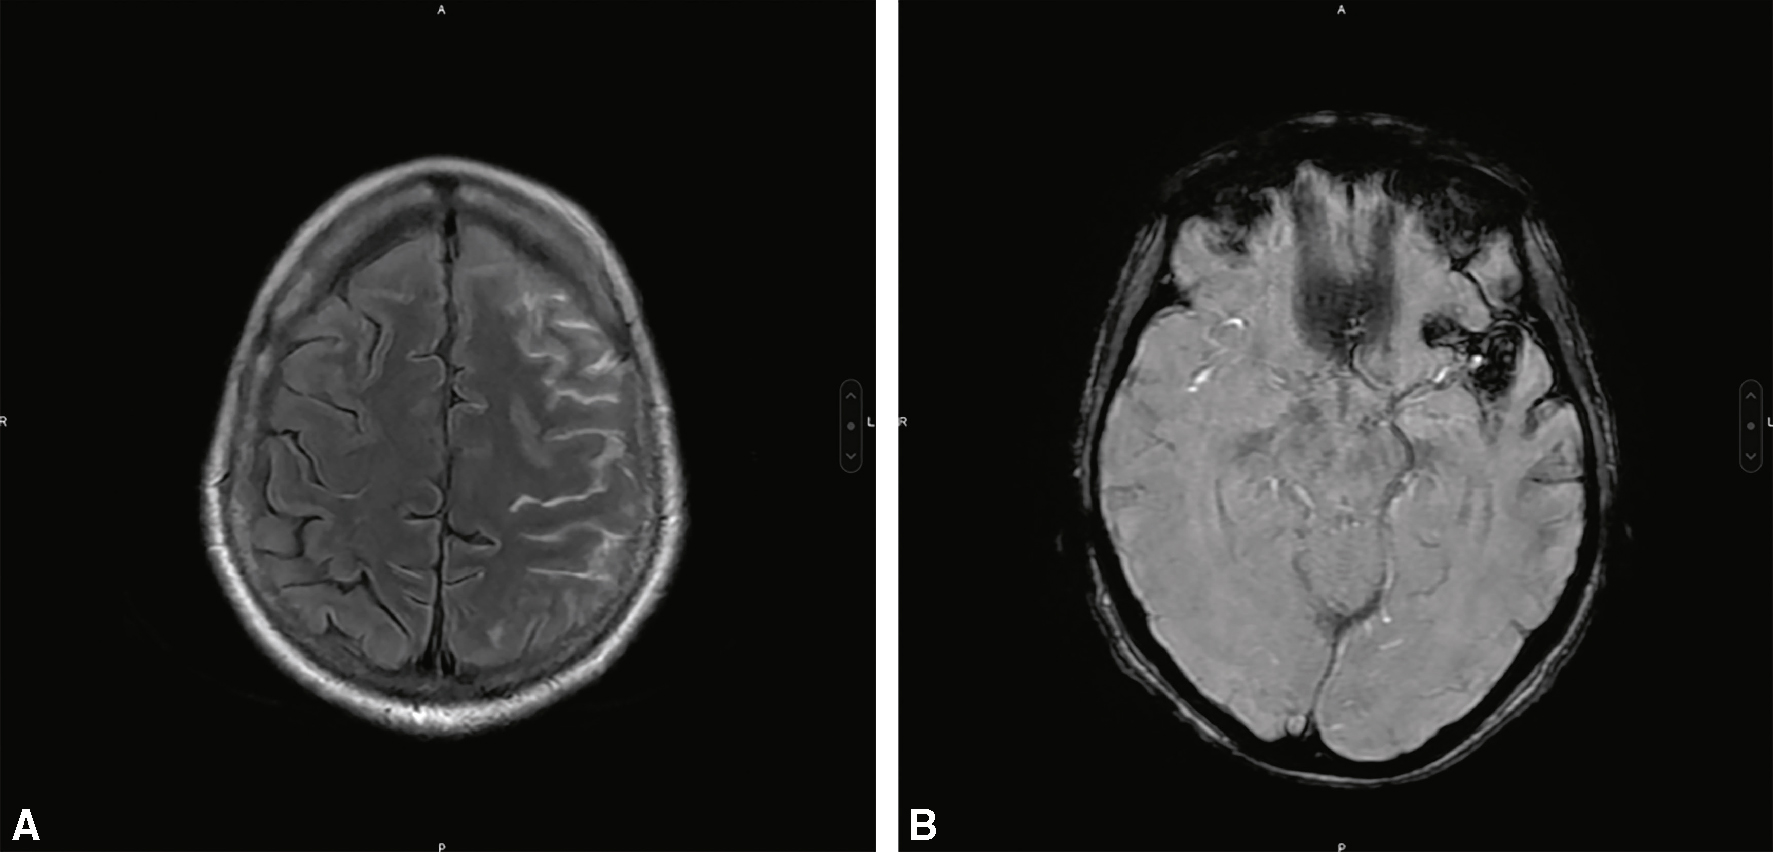

• A meilleure une sensibilité que le scanner dans les jours qui suivent l’HSA avec les séquences FLAIR et T2* (fig. 29.2).

Fig. 29.2

IRM cérébrale montrant une HSA corticale frontale gauche (A : coupe axiale, séquence FLAIR) et de la vallée sylvienne gauche (B : coupe axiale, séquence de susceptibilité magnétique).Ces deux coupes axiales d’IRM cérébrale illustrent une hémorragie sous-arachnoïdienne (HSA) localisée à la convexité. L’image A, en séquence FLAIR, montre un hypersignal diffus au niveau des sillons frontaux gauches, indiquant la présence de sang dans l’espace sous-arachnoïdien cortical. L’image B, obtenue en séquence de susceptibilité magnétique (SWI), révèle plusieurs foyers d’hypo-intensité dans la vallée sylvienne gauche, caractéristiques de dépôts hématiques. L’aspect combiné sur les deux séquences confirme une HSA corticale gauche, probablement d’origine veineuse ou traumatique, en dehors du contexte habituel de rupture anévrismale. Ces images soulignent l’importance des séquences FLAIR et SWI dans la détection précoce et précise des hémorragies corticales.